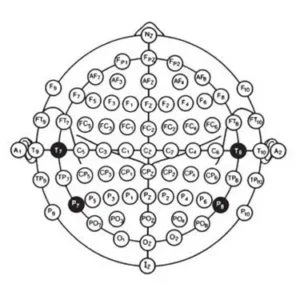

These measurements provided for the location of 19 of the 21 electrodes used in the 10-20 electrode system (fig.5). The remaining two electrodes were placed on the ear loves and labeled auricular electrodes. The electrode positions were named in anatomical terms for the cortical areas rocerded, with the exception of the “C” electrodes which were termed central since they were located over the central sulcus.

A numbering system was added to differentiate between left and right homologous regions, odd numbers for the left hemisphere, Fp1, F3, F7, C3, T3, P3, T5, and O1. Even numbers for the right hemisphere, Fp2, F4, F8, C4, T4, P4, T6, and O2. The original recommendation called the F, C and P vertex electrodes F0, C0, and P0, but later changed to Fz, Cz, and Pz (z for the zero).

The numbers selected allowed for the additional electrodes to be placed in the coronal plane and have suitable designations (e.g. F2 placed between Fz and F4, and F6 placed between F4 and F8). Other additional electrodes included pharyngeal and cerebellar elelectrodes which were termed Pg, Pg2, Cb1, and Cb2, resspectively.

Fig. 6 A single plane projection of the head, showing all standard positions and the location of the rolandic and sylvian fissures. The outer circle was drawn at the level of the nasion and inion. The inner circle represents the temporal line of electrodes. This diagram provides a useful stamp for the indication of electrode placements in routine recording.